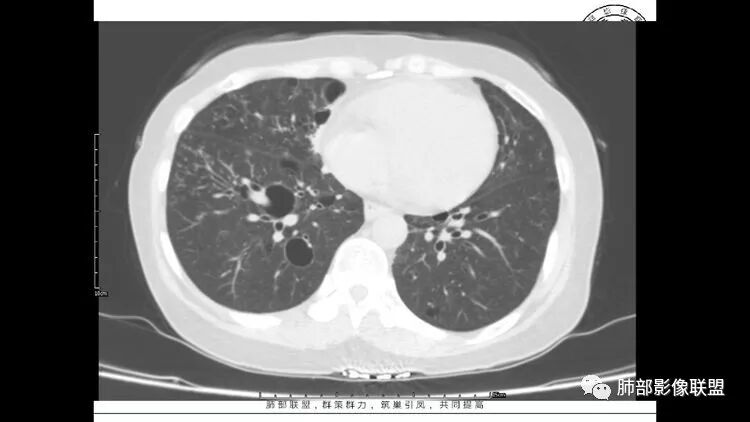

中年女性,因“角膜炎”入院,自用眼液2年,(眼干?)肺部:双肺多发类圆形薄壁气囊+实性结节+GGO,下肺分布为主,纵隔淋巴结肿大,考虑淋巴系统增殖,LIP可能性大,可能继发于干燥综合症;左肺下叶的混合磨玻璃结节形迹可疑,边界清晰,内部疑似空泡,扩张扭曲支气管,极像肺癌,伴双肺转移?待排吧

左肺下叶混杂密度病灶,其内可见空泡,周围ggo清楚,考虑浸润性腺癌。双肺散在多发薄壁囊腔和实性结节,以胸膜下及血管旁分布位于,气囊可见血管贴边征,双肺小叶间隔及中央间质增厚,局部可见磨玻璃影及树芽征,纵隔内淋巴结肿大,考虑LIP

综上,考虑左下肺浸润性腺癌+LIP